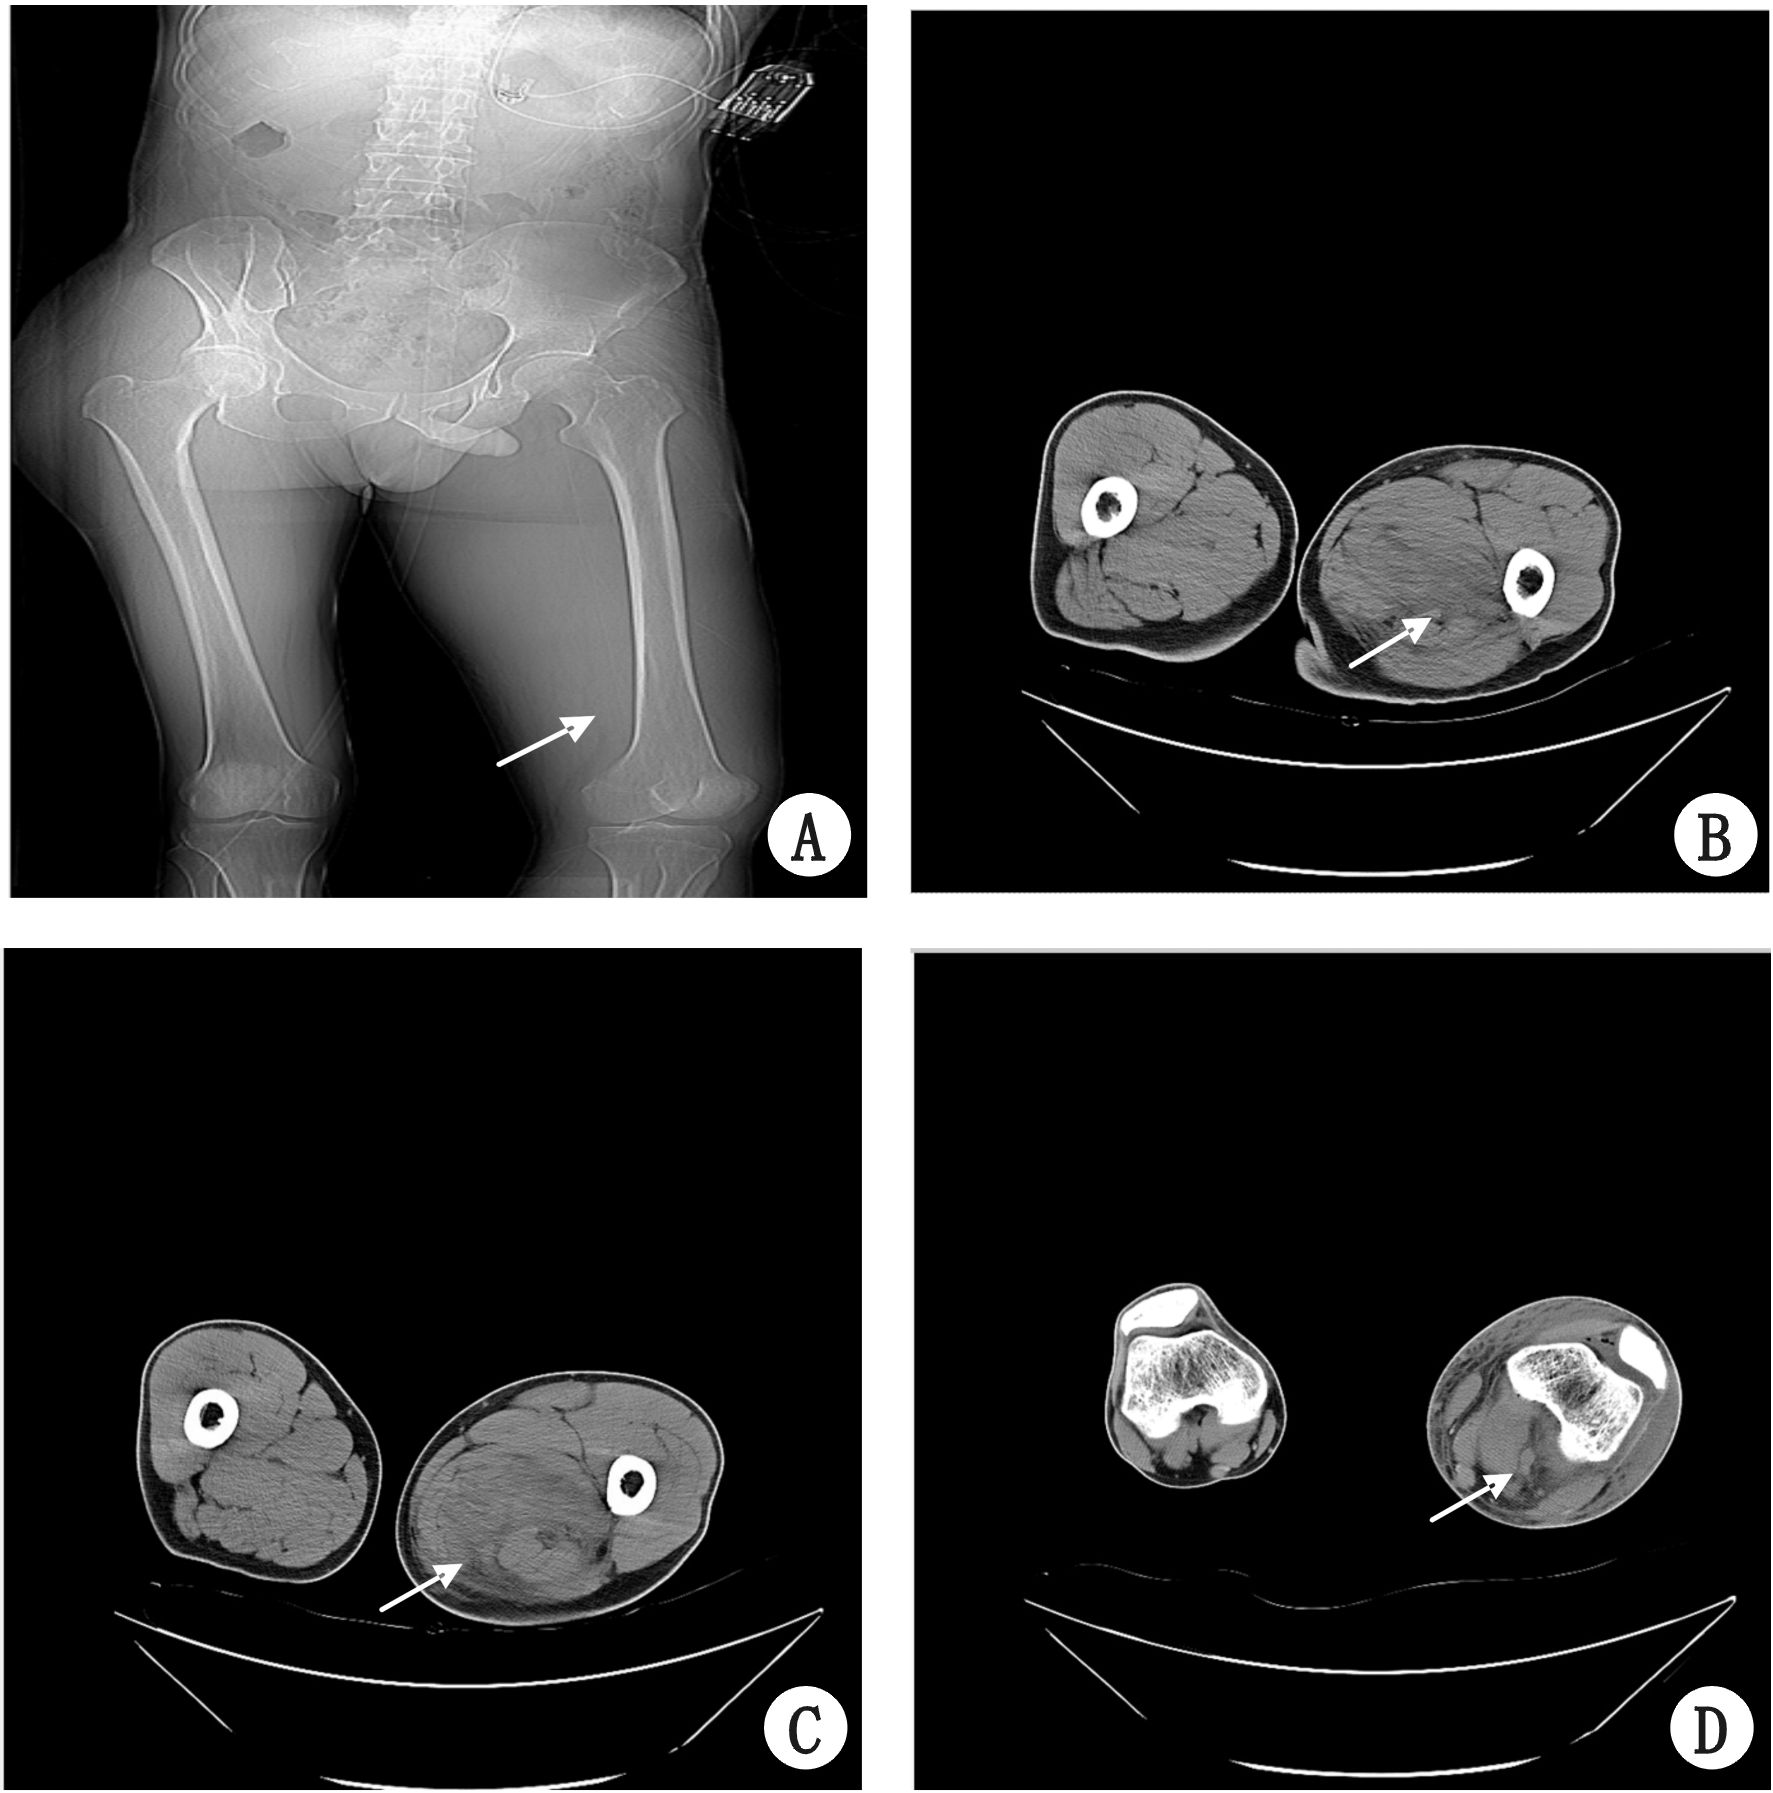

1 资料与方法 患者,男,54岁,2015年12月23日12:59分因“左下肢肿痛4 d”就诊于我院急诊科,患者12月19日无明显诱因出现左下肢膝关节附近肿胀,疼痛进行性加重,否认局部红热,否认外伤,曾有一过性发热,T 38.2 ℃。12月22日上午就诊于我院急诊,查血常规:WBC 17.04×109/L,NEU% 92.6%,Hgb 147g/L,PLT 176×109/L;凝血:PT 15.2 s,APTT 41.3 s,D-二聚体0.66 mg/L。左下肢血管彩超:左小腿肌间低回声,血栓待除外。考虑左下肢静脉血栓可能,给予克赛6 000 U一次治疗,患者左小腿肿胀从膝关节附近延伸至小腿中下段,疼痛逐步加重,患者左踝活动仍好。至夜间约21时30分,左下腿肿胀延伸至左足部,疼痛逐步消失,左踝无法活动(图 1A),查血管彩超,提示:双侧股总、股浅、腘及胫前、胫后动脉内-中膜欠光整,管腔内血流通畅,充盈好,频谱及流速未见异常,左侧腘、胫后、肌间静脉手压变细,彩色血流显像提示血液回流尚通畅。血管外科会诊,考虑非血管栓塞。骨科会诊,建议完善双下肢CT。22时15分,患者突然出现脉速、四肢远端湿冷等休克表现,查PCT>10 ng/mL,考虑感染性休克,给予积极抗感染、纠正休克等治疗,患者左小腿肿胀进一步加重,并逐步出现张力性水泡,肿胀范围逐步延伸向左侧大腿内后侧。 12月23日9时20分左右,复查左下肢血管彩超,提示左侧股总、股浅、胫后动脉内-中膜不光整,散在条状强回声,股浅静脉部分管腔受压变窄,较窄处管腔内径约0.23 cm。考虑存在左小腿骨筋膜室综合征,为行急诊手术入院。既往患者间断排便出血1年,于外院行肠镜活检,病理提示为直肠中分化腺癌,拟近期行择期手术治疗。糖尿病10年,口服拜糖平控制平稳。个人史:吸烟史5年,约1包/日,其余婚育史、家族史无殊。入室查体:T 35.3℃;P 139次/min;R 38次/min;BP 184/105 mmHg(1 mmHg=0.133 kPa);SpO2 99%;呼吸机(VC模式:VC 450 mL,PEEP 5 mmHg,FiO2 40%,SpO2 96%),肾上腺素0.5 μg/(kg·min)维持,全身皮肤可见花斑,左下肢膝关节向下小腿肿胀明显,张力大,表面可见张力性水泡,皮温低,色暗红(图 1B)。左大腿下段的内侧可见肿胀、皮肤色猩红,局部张力不高,余四肢未见明显异常。双肺CT可见散在渗出,腹盆CT可见肠管扩张有积液,双下肢CT膝关节至髋关节弥漫肌肉水肿(图 2)。入室考虑诊断:左小腿骨筋膜室综合征、感染性休克、直肠癌、糖尿病、肾功能不全。

诊疗经过:患者于12月23日全麻下行左小腿骨筋膜室切开减压、VSD负压吸引术,术中可见皮下组织内有淤血,肌肉张力大,颜色为暗红,未见明显坏死、感染病灶,取少许肌肉送病原学检查,咽拭子取病原学检查。术后继续予泰能、斯沃抗感染,抗休克等处理,左下肢明显肿胀,左腹股沟区以下,左下肢内侧可见大片皮肤剥脱、散在水疱、渗液(图 1C),左膝关节以下包扎好,留置引流管左右各1根,VSD持续负压吸引,可吸出暗红色血性液。行骨科、基本外科、血管外科、感染科、重症医学科多科会诊:左下肢蜂窝组织炎、感染性休克、骨室筋膜综合征诊断明确,目前骨筋膜室综合征所致肌溶解、高钾血症均有出现,疾病进展快,侵蚀性强,故致病菌考虑为侵蚀性强的外源性细菌可能性大,不排除产气荚膜菌可能,继续予泰能、斯沃抗感染,保持引流通畅,12月23日19:23予以Swan-Ganz导管监测,右心房、肺动脉、肺动脉嵌顿压波形良好,首次CO 4.2 L/min,CVP 7 mmHg,PAWP 10 mmHg,SVRI 1 400,连续血液透析+滤过治疗,间断输同型红细胞、血浆、血小板、人纤维蛋白原治疗,多次血常规、生化、凝血见表 1~3。12月24日上午10:10细菌室报告需氧瓶肌肉标本涂片有革兰阳性球菌较多(A群β溶血链球菌)。查阅文献[1-3],患者中毒性休克综合征、坏死性筋膜炎等表现亦相符,故目前考虑A组链球菌感染可能性大,加用青霉素、克林霉素和万古霉素加强抗感染处理。患者全身瘀斑及水疱仍有进行性扩大至头面部,全身肿胀亦进行性加重,血小板进行性下降,凝血功能持续恶化,复查血气分析示pH 7.193,PaCO2 47.4 mmHg,PaO2 84.9 mmHg,Lac 18 mmol/L,K+5.6 mmol/L,Ca2+1.01 mmol/L。Swan-Ganz导管监测示CCO 4.5 L/min,SV 48 mL/b,CVP11 mmHg,PAWP15 mmHg,DO2 602 mL/min、VO2 136 mL/min。17:48患者出现心搏停止,家属拒绝行胸外按压及电除颤,宣布患者临床死亡。死亡原因:患者蜂窝组织炎引起感染性休克致多器官功能衰竭。